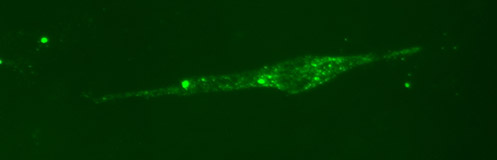

Cells infected with rabies virus were stained with antibodies from rabies-immunized animals. These cells can be seen by stimulating a fluorescent dye attached to the antibodies, which glows green.

Source: PEI

Cells infected with rabies virus were stained with antibodies from rabies-immunized animals. These cells can be seen by stimulating a fluorescent dye attached to the antibodies, which glows green.

Source: PEI